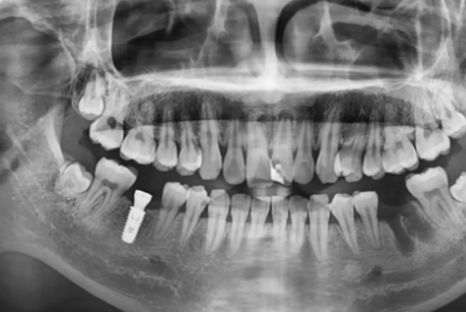

[스마일디 임플란트 사례 중 일부]

치료기간: 23.12.25일-24.06.28 (약 6개월)

진행한 치료: 발치 후 염증치료, 골이식과 임플란트2개 식립후 브릿지

치료기간: 24.11.03일-24.12.03(약 1개월)

진행한 치료: 발치 후 임플란트

*치료 전후 사진은 환자의 동의하에 게재하였으며, 동일한 환경과 조건에서 촬영된 전후 사진입니다.